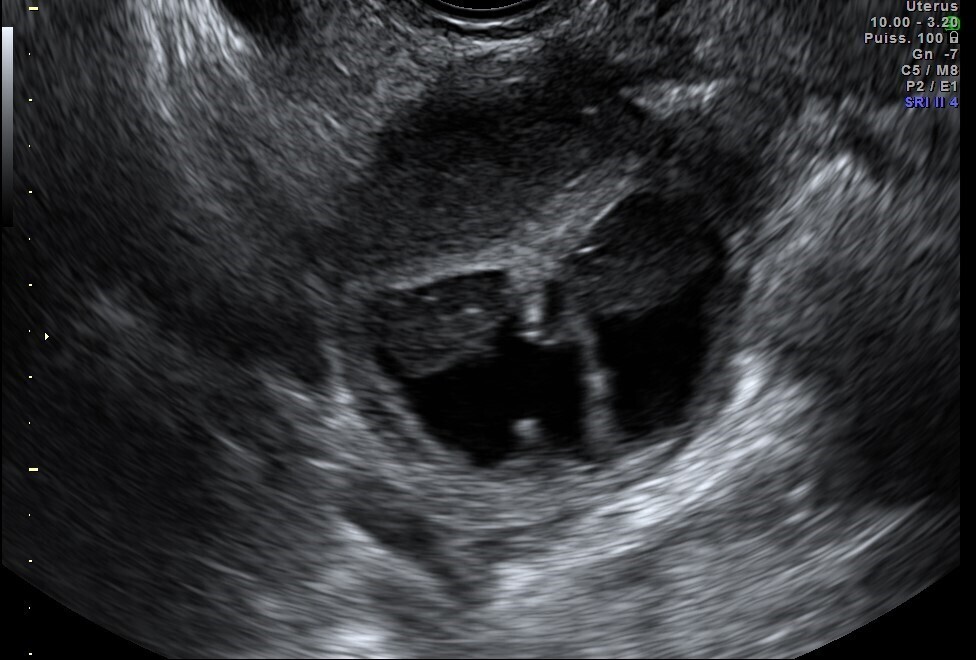

Vous faites une échographie pelvienne qui retrouve un utérus antéversé avec un endomètre épaissi de 5 mm, des ovaires droit et gauche sans anomalie. Il n’y a pas d’épanchement dans le cul-de-sac de Douglas.

On note l’absence de kyste sur les ovaires, même affaissé, associée à un cul-de-sac de Douglas sec.